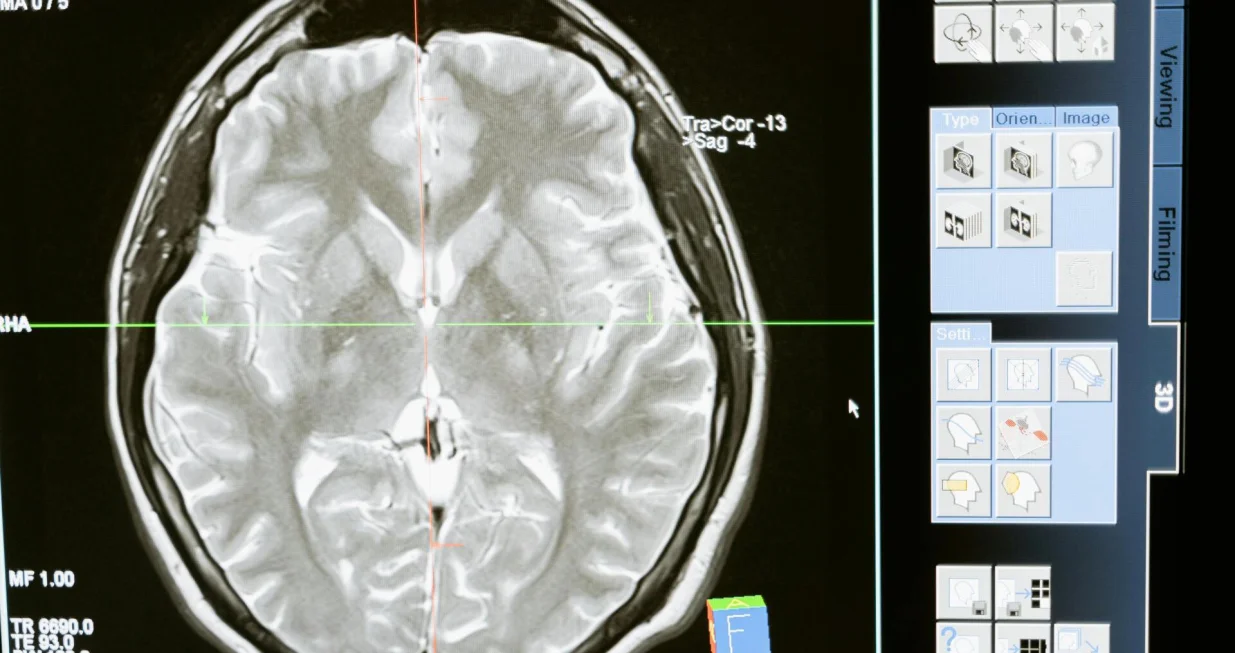

Studija pod nazivom "Pojačana interakcija neuronske koherentnosti i povezivanja u umirućem ljudskom mozgu", objavljena u časopisu Frontiers in Aging Neuroscience, pokazuje da mozak može ostati aktivan i organizovan čak i nakon što srce prestane kucati, piše

Istraživači su sasvim slučajno došli do ovog otkrića dok su mjerili moždane talase 87-godišnjeg pacijenta koji je bolovao od epilepsije. Tokom snimanja, pacijent je doživio fatalni srčani udar, pruživši tako rijetku priliku za bilježenje moždane aktivnosti u posljednjim trenucima života.

Naučnici su analizirali 900 sekundi moždane aktivnosti prije i nakon smrti, otkrivši da su u posljednjih 30 sekundi prije i poslije prestanka rada srca moždani talasi pacijenta pratili obrasce slične sanjanju i prisjećanju.